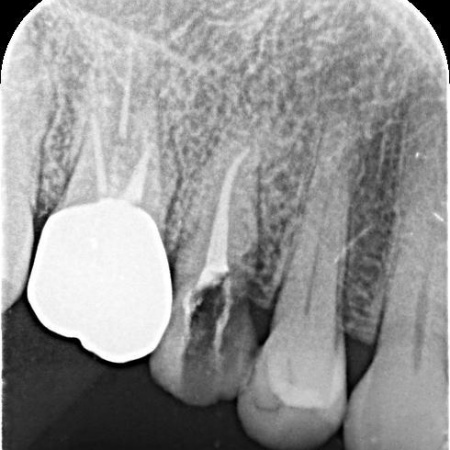

レントゲン撮影をして詳しく拝見したところ、右上奥歯の頭部分「歯冠」が縦に割れる「歯冠の垂直破折」が確認できました。

割れ目が深い場合は、歯の温存が困難です。

今回の症例では、症状や割れ方に応じて治療方針を慎重に判断する必要があると診断しました。

1:細菌感染した神経を取り除いてから薬を詰める「根管治療」

まず、割れている部分をしっかりと確認し、必要な部分を除去してから根管治療を行います。

薬剤を歯根の先までしっかりと詰め、支台築造で土台を作製したあと、被せ物を作製しました。